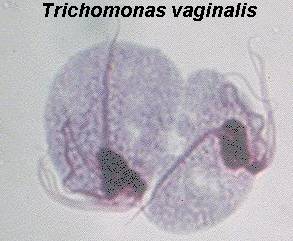

BTS

provocate de protozoare Trichomonas

Ce este?

Trichomonas este o infectie obisnuita a vaginului. Unele femei pot observa o

crestere a secretiilor vaginale care poate mirosi urat si care pot avea o

culoare alb-galbuie sau verzui-galbena. Multe femei nu au nici un semn al

bolii. Barbatii pot lua si ei boala si pot servi si ca purtatori.

Cum se depisteaza?

La microscop, trichomonas se poate vedea cum se misca in secretiile

colectate din vagin sau uretra.